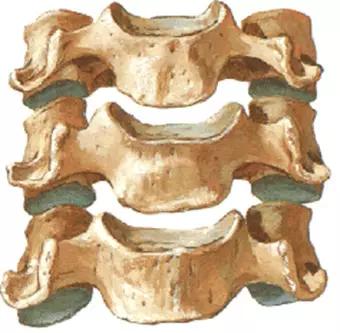

人体的脊柱,是由7块颈椎、12块胸椎、5块腰椎、1块骶骨和1块尾骨组成。每一节椎骨与相邻的椎骨之间都是通过复杂的关节、韧带以及椎间盘相互连接的。从前面看脊柱成一条直线,从侧面看有四个生理弯曲。

椎体、椎板、椎弓根、关节突、横突、棘突。